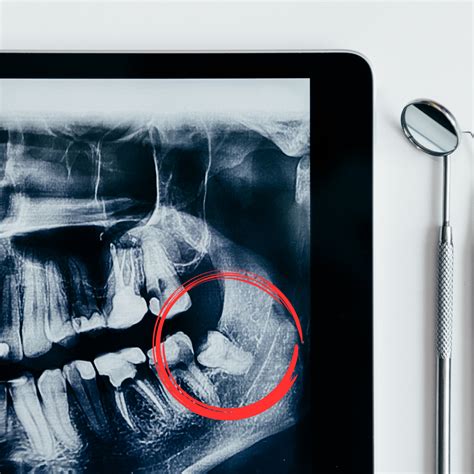

El dolor de las muelas del juicio puede deberse a diferentes causas. Al ser los últimos en aparecer, en ocasiones, nuestra boca no tiene espacio suficiente para alojarlos y quedan retenidos, produciéndonos dolor e hinchazón en esa zona.

El dolor de la muela del juicio puede suceder porque, durante el proceso de erupción, la pieza dental no cuenta con espacio suficiente para salir. Esto puede deberse a que el resto de dientes ya han erupcionado y a que la muela del juicio se localiza en la parte posterior de la boca.

Si las muelas del juicio no emergen con normalidad, quedarán atrapadas en la mandíbula. Se estima que, aproximadamente, el 90% de las personas experimentan ciertas complicaciones cuando salen las muelas del juicio.